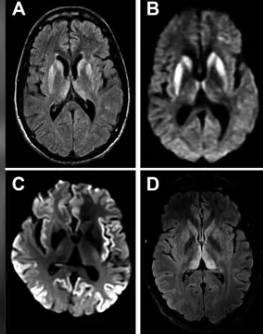

![약 50년 전 범뇌하수체기능저하증으로 사체의 장기에서 추출한 호르몬을 투여 받은 여성이 크로이츠펠트 야곱병으로 숨졌다. 사진은 크로이츠펠트 야곱병 환자의 뇌 MRI 영상. [Practical Neurology 캡쳐]](https://img1.daumcdn.net/thumb/R658x0.q70/?fname=https://t1.daumcdn.net/news/202505/28/KorMedi/20250528134456213drjj.jpg)

그녀는 MRI(자기공명영상) 검사 결과 뇌 손상이 발견됐고 추가 검사에서 '프리온' 단백질 양성으로 밝혀졌다. 프리온은 세포를 둘러싼 세포막에 있으며 세포 통신 및 상호 작용에 관여하는 분자다.

그녀는 프리온에 의해 발생하는 희귀하고 치명적인 '크로이츠펠트-야콥병(CJD)' 진단을 받았다.